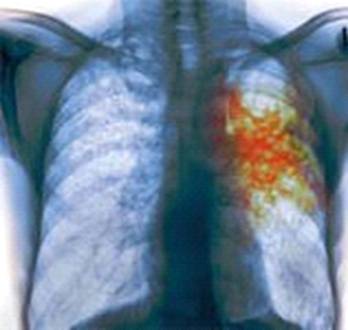

Рис. Лёгкие человека, болеющим туберкулезом